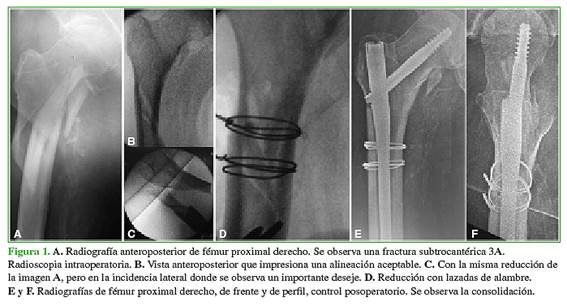

Todos los pacientes fueron operados en el mismo centro, por el mismo equipo quirúrgico, en una mesa de tracción bajo radioscopia. Inicialmente siempre se trató de lograr la reducción cerrada de la fractura. Cuando no fue posible, se procedió a la apertura del foco con un cuidadoso manejo de partes blandas y luego a la reducción directa y la colocación de cerclaje de alambre (Figura 1). Se utilizaron siempre alambres de 1,5 mm de diámetro.

El subtipo de fractura en el que más usamos lazadas fue el 3A de la clasificación de Seinsheimer. En este patrón de fractura, lo que suele ocurrir es que, al efectuar la reducción en la mesa de tracción, cuando se procede al control en la proyección anteroposterior, la fractura puede impresionar alineada, pero, al evaluar la proyección lateral, esto no es así, y hay un importante deseje (Figura 1). Este deseje no siempre es posible de reducir con manipulación externa, palancas o incluso con el mismo clavo, y requiere la apertura del foco y la reducción con lazadas.